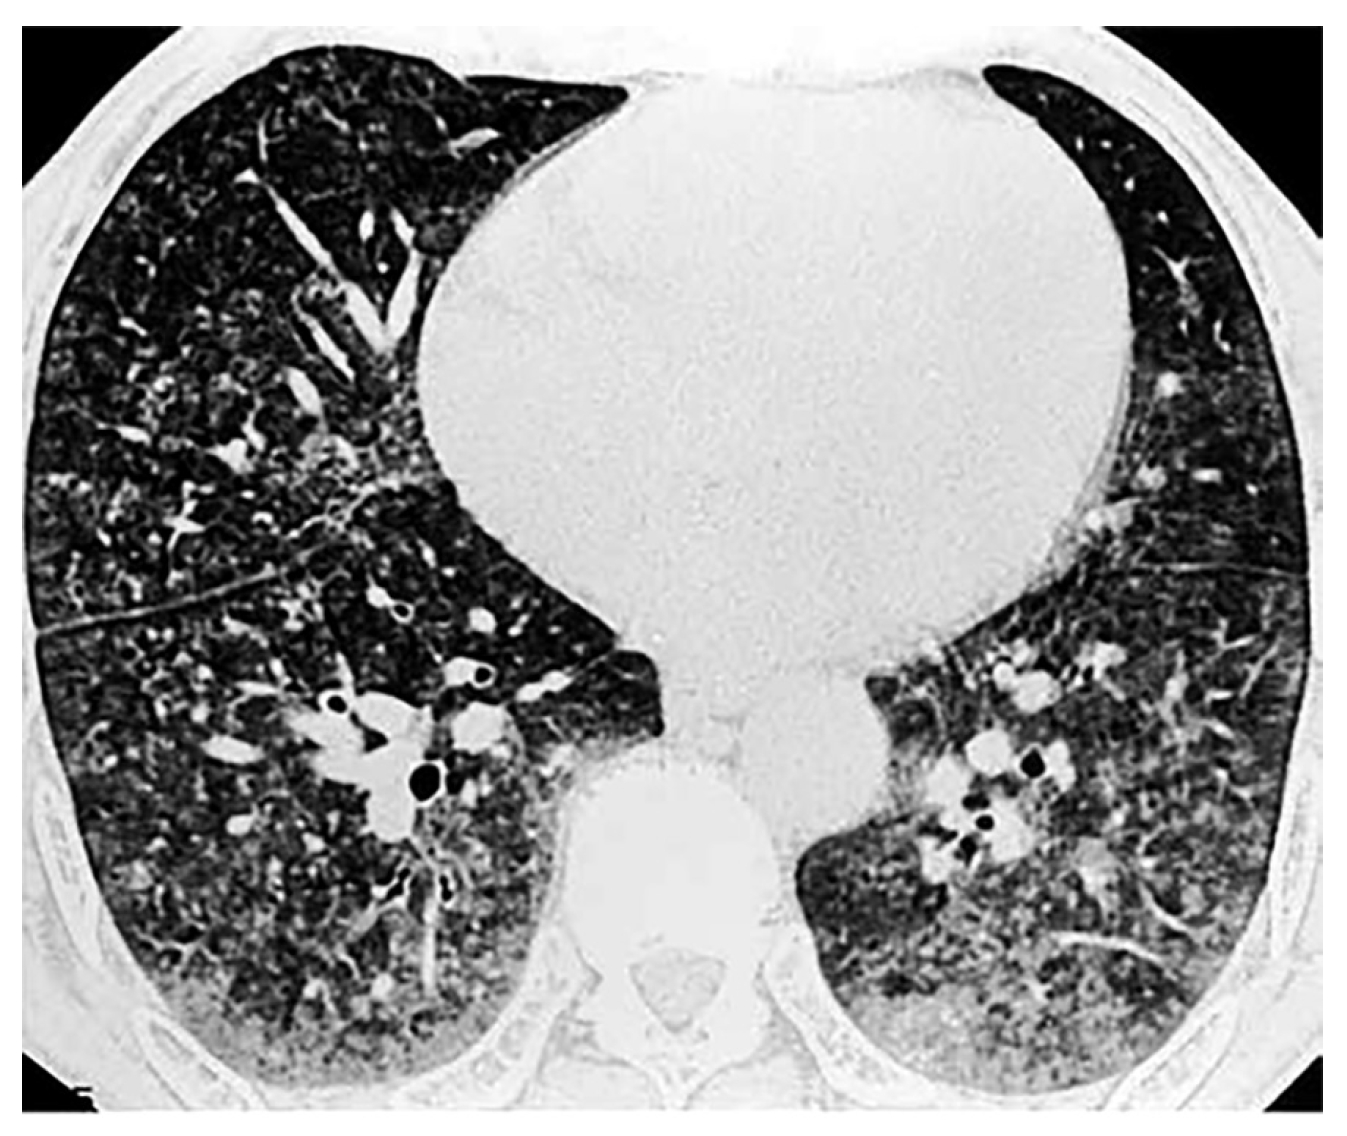

Рентгенологически выявляются интерстициальный ветвисто-сетчатый фиброз (2s) и мелкие (2р) узелковоподобные тени, расположенные преимущественно в средних и нижних отделах и на периферии. В латеральных отделах имеются узелки с тенденцией к слиянию в более крупные (q). Обнаружены рассеянные обызвествленные очаги в нижних отделах в диаметре 0,3–0,5 см больше справа. Корни уплотнены, расширены. Определяется повышенная прозрачность легочных полей в верхних долях (рис. 1).

Рис. 1. Рентгенограмма грудной клетки больного К.